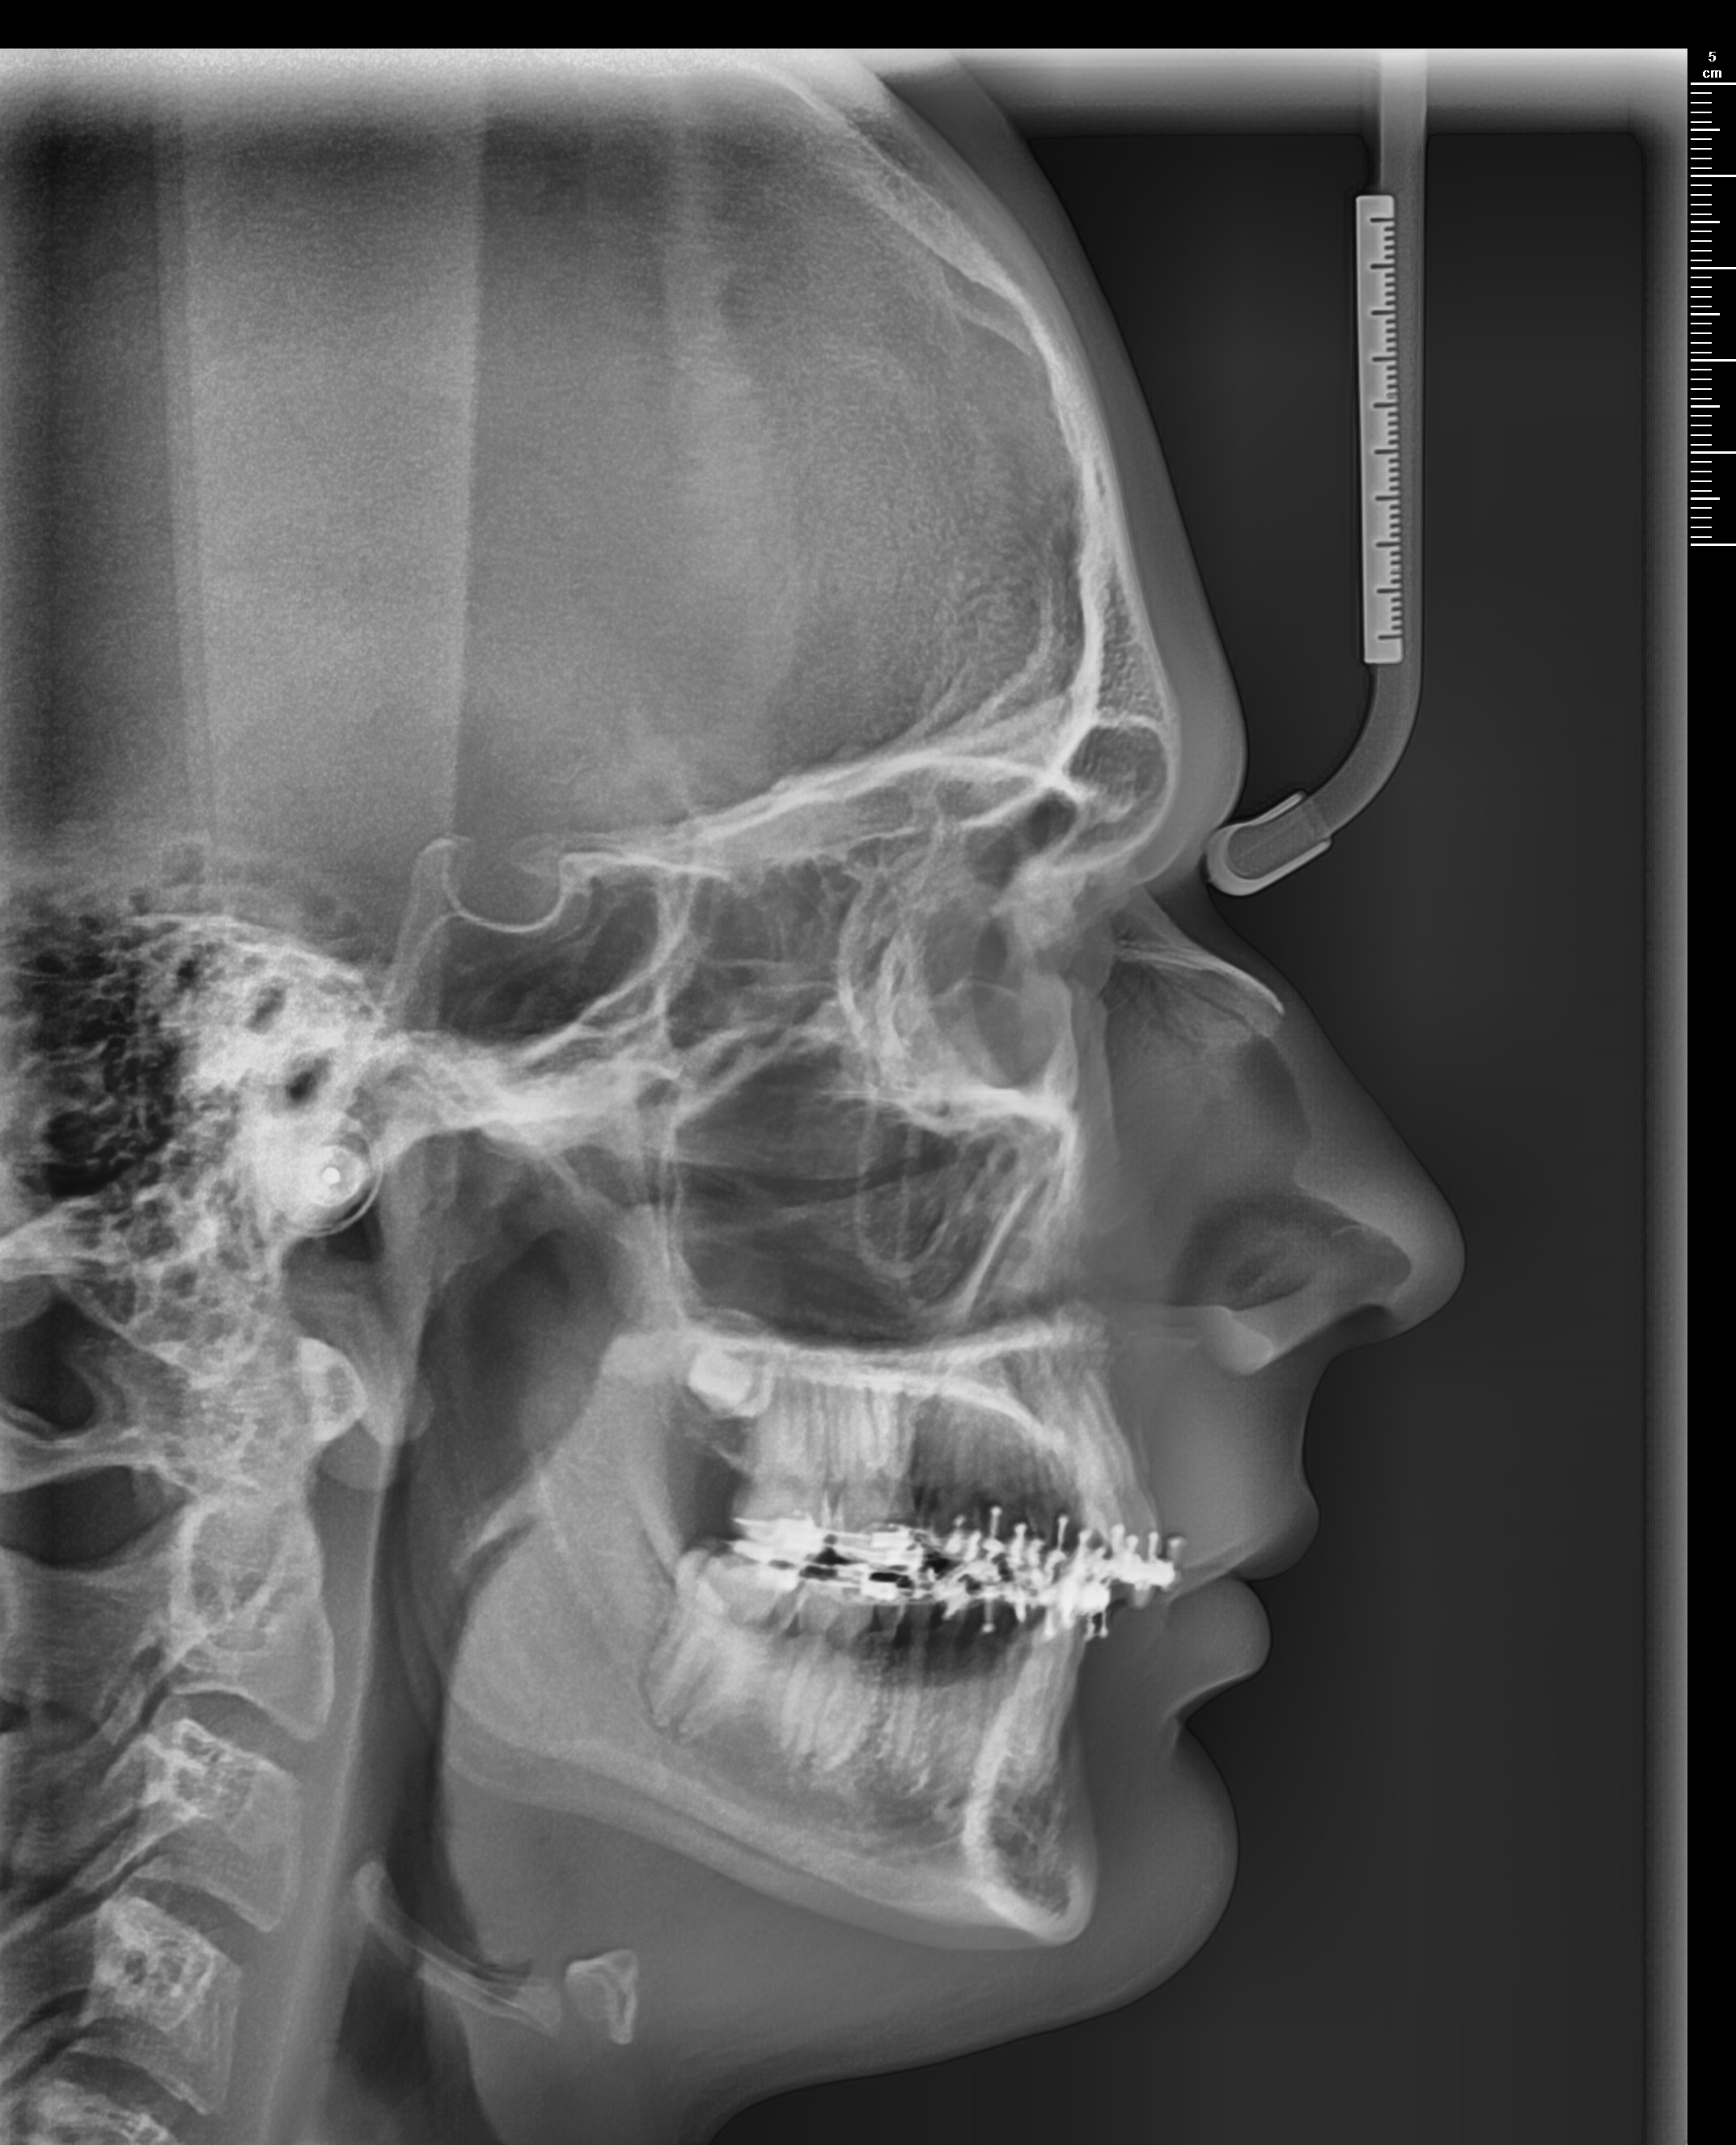

Got a Bimax late september via insurance. These were the movements planned.

LEFORT 1: 2MM ADVANCEMENT

BSSO: 8MM ADVANCEMENT

2° CCW ROTATION

PRE BIMAX

My question is: Did I get underadvanced? I'm aware swelling takes longer to go away but atm I still feel like my jaw is recessed.